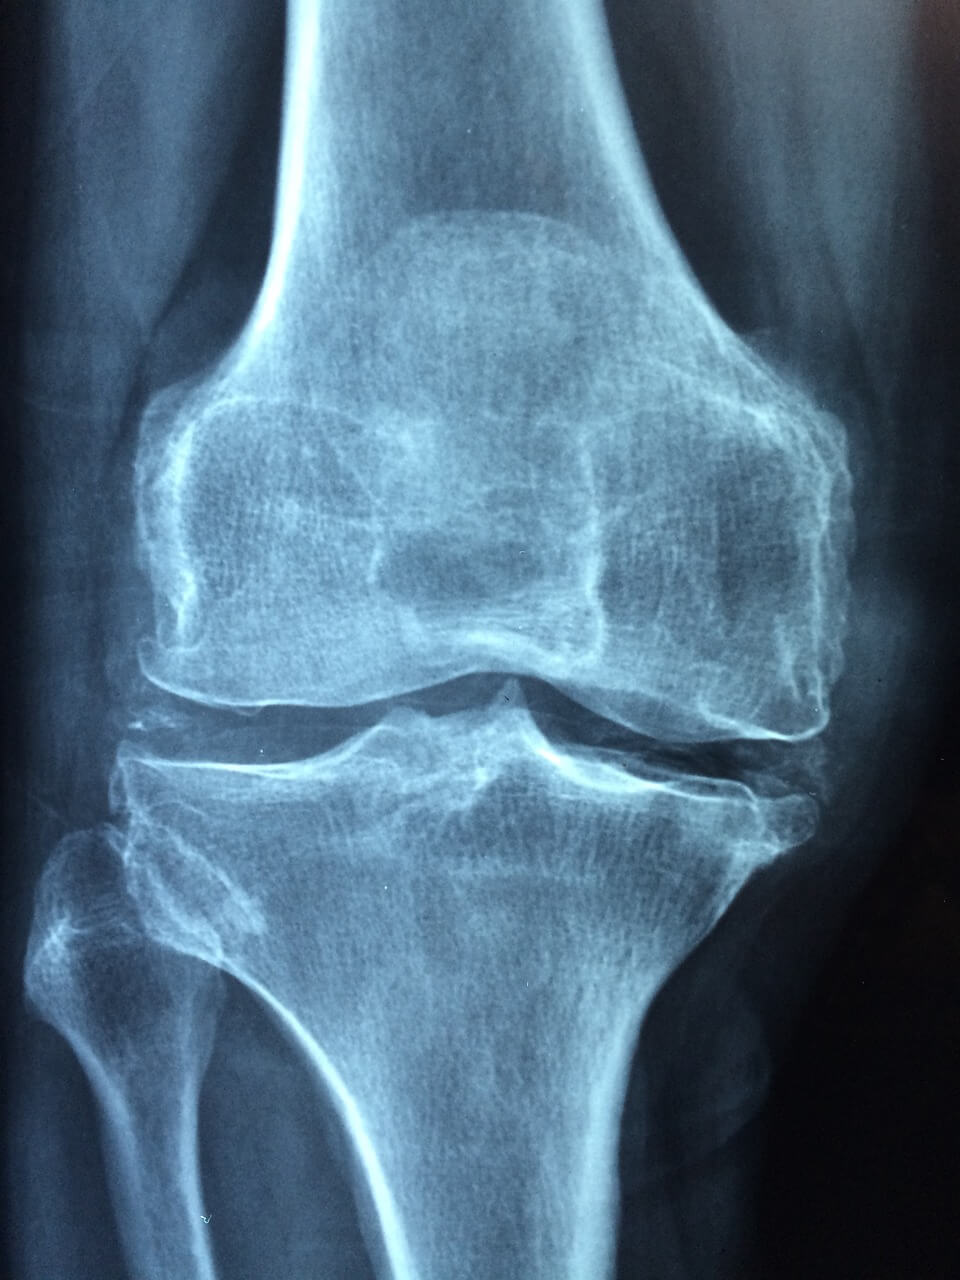

퇴행성 관절염 원인 밝혀내기

퇴행성 관절염의 근본 원인을 파악하면 관절염에 미치는 피해를 관리하고 완화하기 위한 조치를 취할 수 있습니다.

정확한 원인은 다양하지만 다음과 같은 요인들이 영향을 미치는 것으로 알려져 있습니다.

나이: 나이가 들면서 관절을 완충하는 연골이 자연적으로 분해되기 시작하여 퇴행으로 이어집니다.